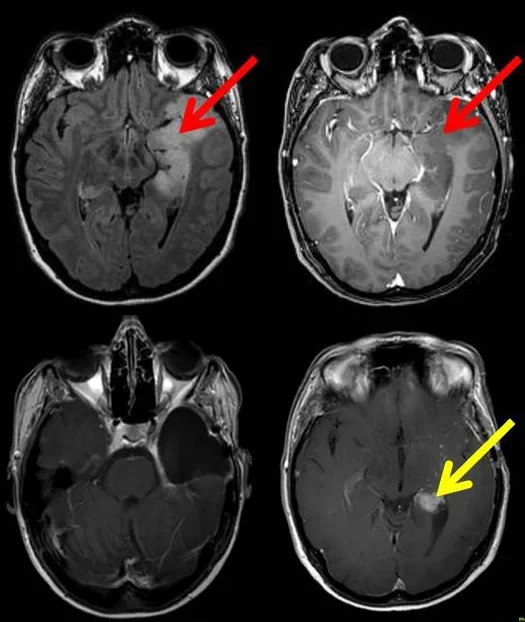

Bilder des Gehirns einer Patientin mit einem Gliom

(rote Pfeile; obere Reihe), das bereits zum Zeitpunkt der ersten Operation begonnen hatte zu entarten. Untere Reihe: Nachgewachsener, jetzt sehr bösartiger Tumor (gelber Pfeil).